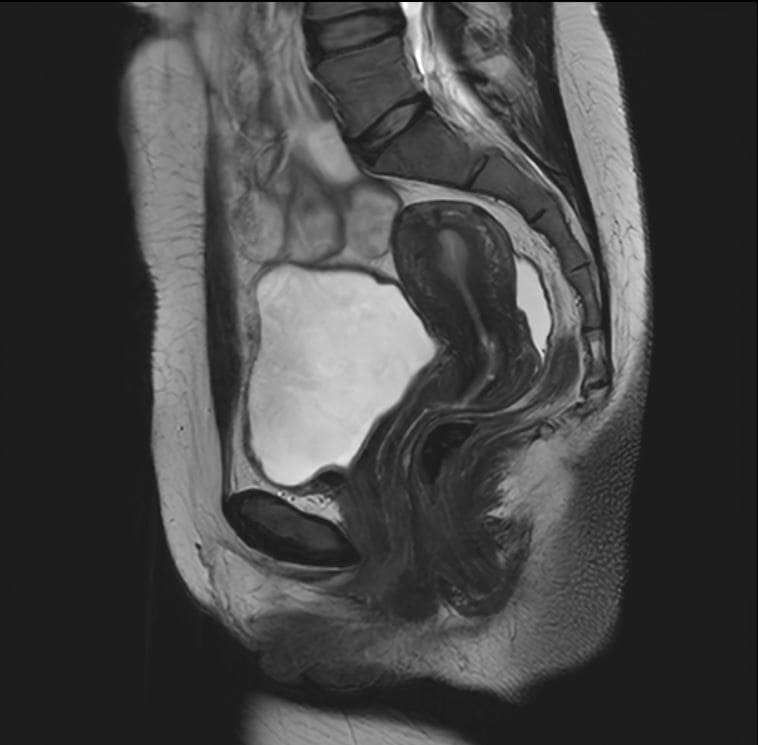

Eksempler på MR Scanninger

En gynækologisk MR-scanning af kvindelige kønsorganer er en skånsom og præcis undersøgelse, der giver detaljerede billeder af underlivet. Vores 3 tesla MR-scanner bruger et magnetfelt og radiobølger til at skabe tydelige billeder af bløddele som livmoder, æggestokke og omkringliggende væv – helt uden brug af røntgenstråling.

Denne type undersøgelse er særligt god til at undersøge og diagnosticere forskellige tilstande i underlivet, der kan være svære at opdage med andre metoder. MR-scanning kan give et klart og detaljeret billede af eventuelle forandringer eller sygdomme i de kvindelige kønsorganer.